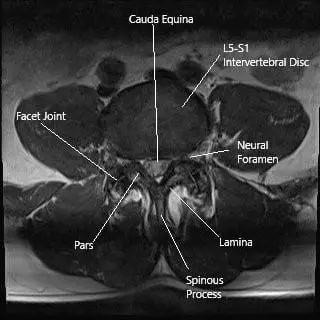

Each vertebra has two pairs of facet joints—one connecting to the vertebra above and one to the vertebra below. They act as hinges, guiding spinal motion while preventing excessive twisting.

The joint surfaces are lined with cartilage and surrounded by a capsule that produces synovial fluid, keeping the joint lubricated. When cartilage thins or the capsule becomes inflamed, the smooth motion is lost and pain signals are sent through tiny medial branch nerves.

Axial section of the lumbar spine showing the facet joints.